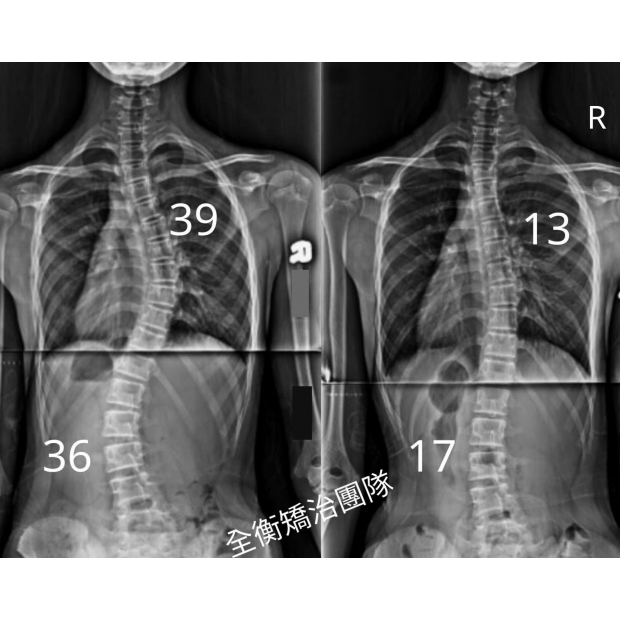

側彎並不可怕, 早期發現早期治療,是成功矯正的關鍵!S型脊椎側彎女孩側彎並不可怕, 早期發現早期治療,是成功矯正的關鍵!S型脊椎側彎女孩

13歲S型側彎女孩

胸椎39度進度到13度

腰椎36度進度到17度